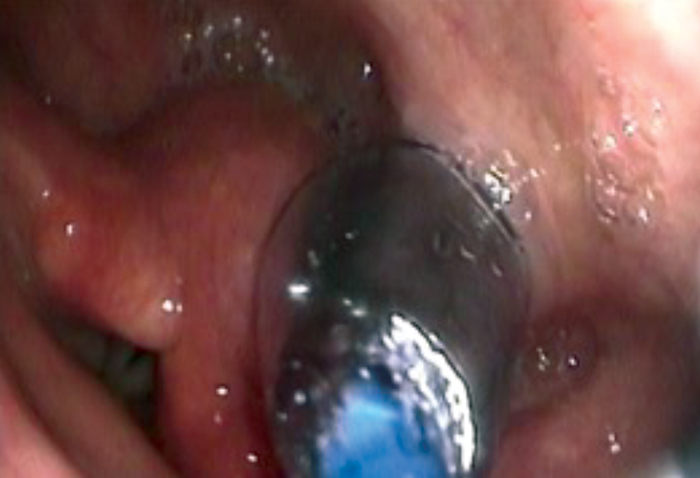

Once the tip of the guide wire is placed beyond the stricture, the TNO is reintroduced nasally via the most patent nasal cavity to visualise the pharynx during the dilatation. The uninflated balloon is then passed over the guide wire nasally until it passes through the area to be dilated. Both TNO and the balloon cables may be passed via same nostril if the other nostril is too narrow. The balloon is positioned with the proximal metallic silver marker visible just above the level to be dilated (see Figure 5). The balloon is then inflated using the pressure pump syringe until 20mm full dilatation (see Figure 6). This is then deflated after one minute and the balloon is removed with the guide wire. In some cases of webbing or cricopharyngeal bar, two 20mm balloons (40mm maximum) may be used simultaneously (see Figure 7). However, this carries a higher risk of perforation and it is more painful and, therefore, will need sedation in addition to the local anaesthesia.

Figure 6. Single balloon dilatation of a cricopharyngeal web.